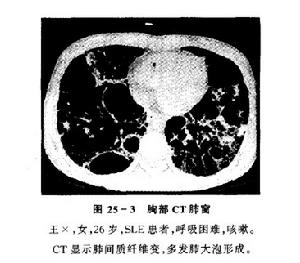

间质性肺炎肺纤维化

间质性肺炎ct表现

间质性肺炎ct